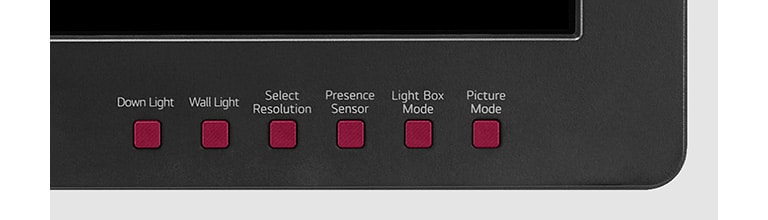

Intuitive Control

YES(6keys)